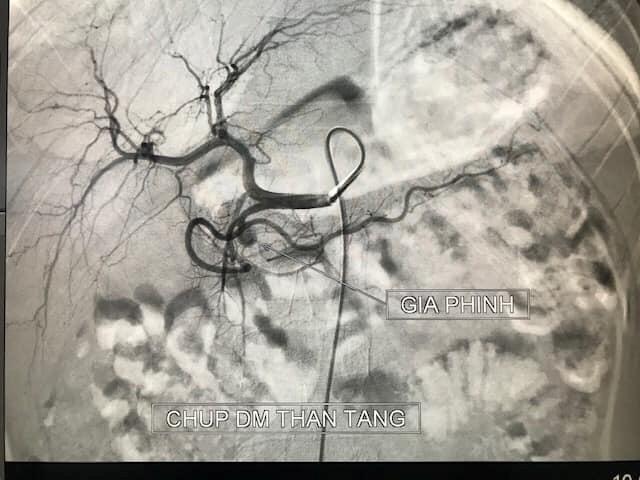

Kết quả trên phim chụp cắt lớp vi tính cho thấy ổ giả phình lớn động mạch vị tá tràng (có chức năng cung cấp máu cho tá tràng - tụy và dạ dày).

Sau khi hội chẩn, các bác sĩ nhận định đây là trường hợp nặng, nguy cơ chảy máu ồ ạt đe dọa tính mạng người bệnh. Bệnh nhi đã được can thiệp cấp cứu ngay sau đó. Sau 20 phút can thiệp với 5 coils ổ giả phình đã được loại bỏ hoàn toàn.

Hình ảnh ổ giả phình lớn động mạch vị tá tràng ở bệnh nhân.

Hình ảnh sau nút mạch cho bệnh nhân.

Can thiệp mạch là phương pháp được lựa chọn để điều trị các tổn thương giả phình mạch do viêm tụy cấp với tỷ lệ thành công và độ an toàn rất cao.